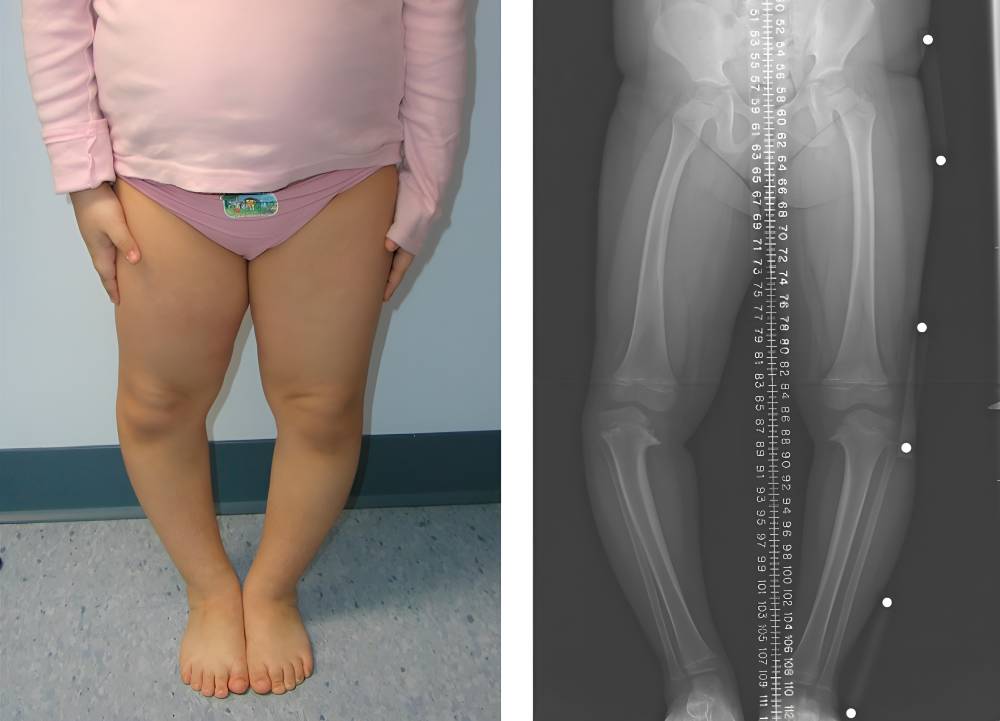

- پای پرانتزی

- زانوی ضربدری

- عکسبرداری: پزشک با عکسبرداری میتواند از تغییر شکل و انحراف استخوانها آگاه شده و میزان ناهنجاری آن را بررسی کند.

اگر نرمی استخوان در کودکان درمان نشود و کودک به سن بلوغ برسد، صفحات رشد بسته میشوند و ناهنجاریهای ناشی از راشیتیسم که شامل ناهنجاریهای دست و پا است به طور دائم باقی میماند. همچنین اگر فرد بزرگسالی به مدت طولانی به استئومالاسی مبتلا بوده و برای درمان آن اقدام نکند ممکن است به ناهنجاری استخوان دچار شود. در این موارد فقط درمان با مکملهای ویتامین و مواد معدنی برای رفع ناهنجاریهای ناشی از نرمی استخوان کافی نیست و بیمار برای رفع عوارض دائمی ناشی از این بیماری نیاز به درمانهای دیگر نیز دارد.

- ناهنجاری استخوان پا و دست